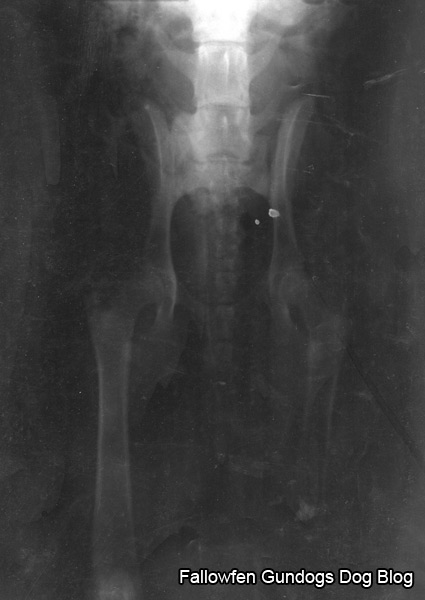

Hip scoring.

Monday, May 26th, 2008Hip scoring is a procedure used to determine the degree of hip dyplasia in dogs.The hip score is the sum of the points awarded for each of nine radiographic tures of both hip joints.The British Veterinary Association uses the following criteria to determine hip score:

- Norberg Angle

- Subluxation

- Cranial Acetabular Edge

- Dorsal Acetabular Edge

- Cranial Effective Acetabular Rim

- Acetabular Fossa

- Caudal Acetabular Edge

- Femoral Head \ Neck Exostosis

- Femoral Head Recontouring

The lower the score, the less the degree of dysplasia present. The minimum (best) score for each hip is zero and the maximum (worst) is 53, giving a range for the total of 0 to 106.